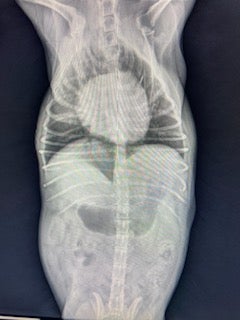

Digital Radiography (X-rays): Clear, high-resolution images help detect fractures, foreign objects, arthritis, tumors, and more.